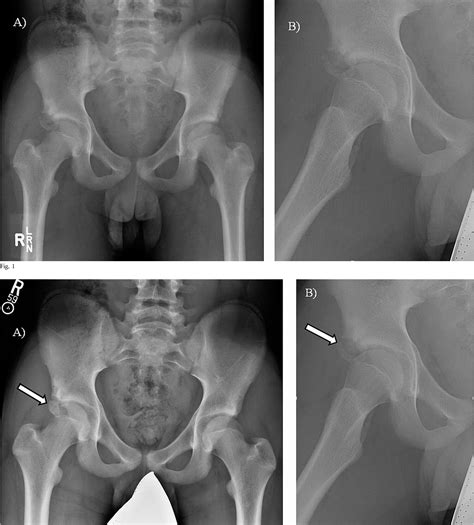

Identifying issues involving the Anterior Inferior Iliac Spine often requires more than just a physical examination. While a physician can test for tenderness through palpation, imaging is necessary to determine the severity of the injury. Standard diagnostic procedures include:

• X-rays: Highly effective for identifying bone fragments resulting from an avulsion fracture.

Injuries to the AIIS are most frequently seen in sports that require rapid acceleration or repetitive kicking, such as soccer, football, and sprinting. The most common type of injury is an avulsion fracture. An avulsion fracture occurs when the muscle contracts so forcefully that it pulls a small piece of bone away from the attachment site.